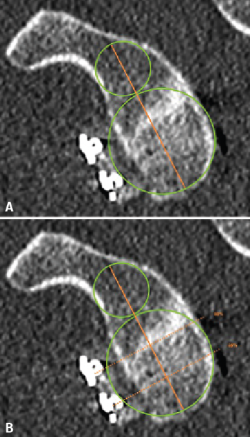

Figure 3. Evaluation of the graft position in the axial view, according to the description of Kany et al.(14). A circumference is traced over the glenoid border, and following the curvature of the latter, the amount of graft (in mm) extending beyond or failing to reach this line is measured. Image A shows the graft perfectly positioned, following the curvature of the glenoid concavity. Image B shows the graft medial with respect to the line. Image C shows the graft positioned too lateral.

The position of the graft in the mediolateral direction was evaluated in the axial sections corresponding to 50% and 25% of the glenoid height. For this purpose we used the curvature method described by Kany et al.(14); on the glenoid border and following its curvature, a circumference was traced and we quantified (in mm) the amount of defect that did not reach or surpassed that line at the point where the graft was closest to the native glenoid cavity (Figure 3). Optimum positioning of the graft was considered when the latter was located in line with the glenoid cavity, up to 3 mm lateral or up to 5 mm medial with respect to the glenoid joint border(14). Grafts protruding more than 3 mm were considered to be located lateral, while those located more than 5 mm medial to the glenoid joint surface were classified as being medial.